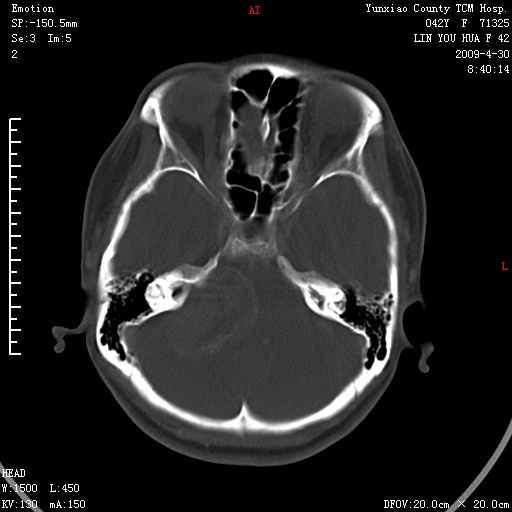

右侧桥小脑角区肿瘤,高密度囊变有显著强化,骨窗见内听道显著扩大,考虑听神经瘤可能性大

1)右侧听神经瘤。2)阻塞性脑积水。

内听道扩大,支持考虑听神经瘤可能性大。